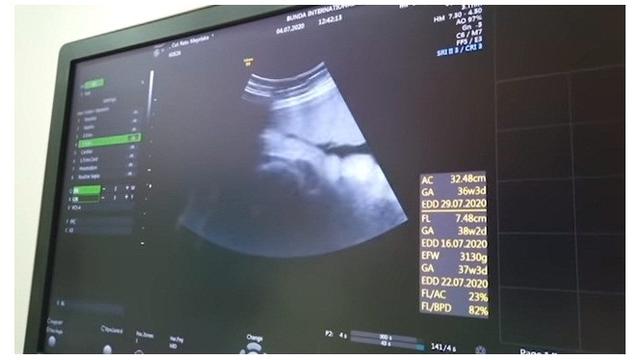

5. Kebahagian pun tetap dirasakan pasangan selebriti ini saat Chika melakukan USG.

6. Keduanya juga cukup penasaran dengan wajah sang buah hati yang tampak malu-malu dan bersembunyi.